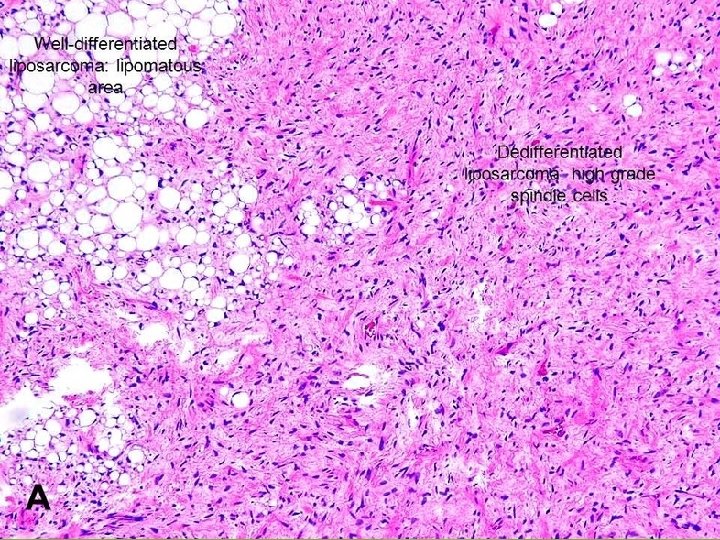

Liposarcoma Malignant neoplasms of adipocyte. Most common in fifth & sixth decades of life. Arise in deep soft tissues or in retroperitoneum. Well-circumscribed lesions. Morphology: Several different histologic subtypes: 1 - Well-differentiated liposarcoma. 2 - Myxoid/round cell liposarcoma: Characterized by abundant mucoid extracellular matrix. 3 - Poorly differentiated tumors.

Prognosis is influenced by the Histologic subtype: Well-differentiated tumors: q Grow slowly. q Associated with more favorable outlook. q Have Good prognosis. Myxoid/round cell & poorly differentiated tumors q. Aggressive tumors. q. Recur after excision. q. Have Poor prognosis.

Well-differentiated liposarcoma.